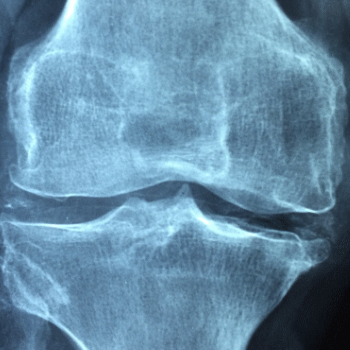

콘드로이친 효능 2. 관절염 증상 완화

콘드로이친은 골관절염과 같은 관절염 질환의 증상을 완화하는 데 효과적입니다. 연구에 따르면, 콘드로이친은 통증과 염증을 줄이고, 관절 기능을 개선하여 삶의 질을 높이는 데 도움을 줍니다. 관절염 환자는 종종 관절 부위의 통증과 뻣뻣함을 겪으며, 콘드로이친은 이러한 증상을 경감시켜 보다 자유로운 움직임을 가능하게 합니다.